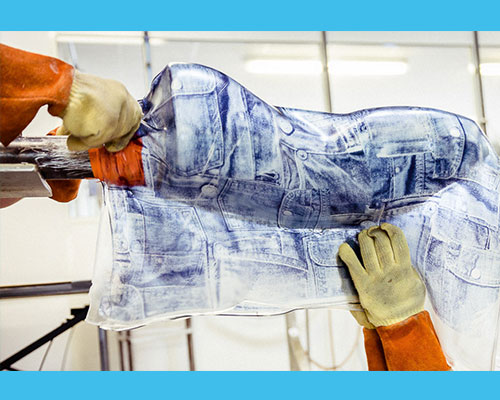

Positif (moulage) :

le moule positif est la reproduction originale du tronc du patient en 3D. Le positif sert pour le thermoformage de l’orthèse.